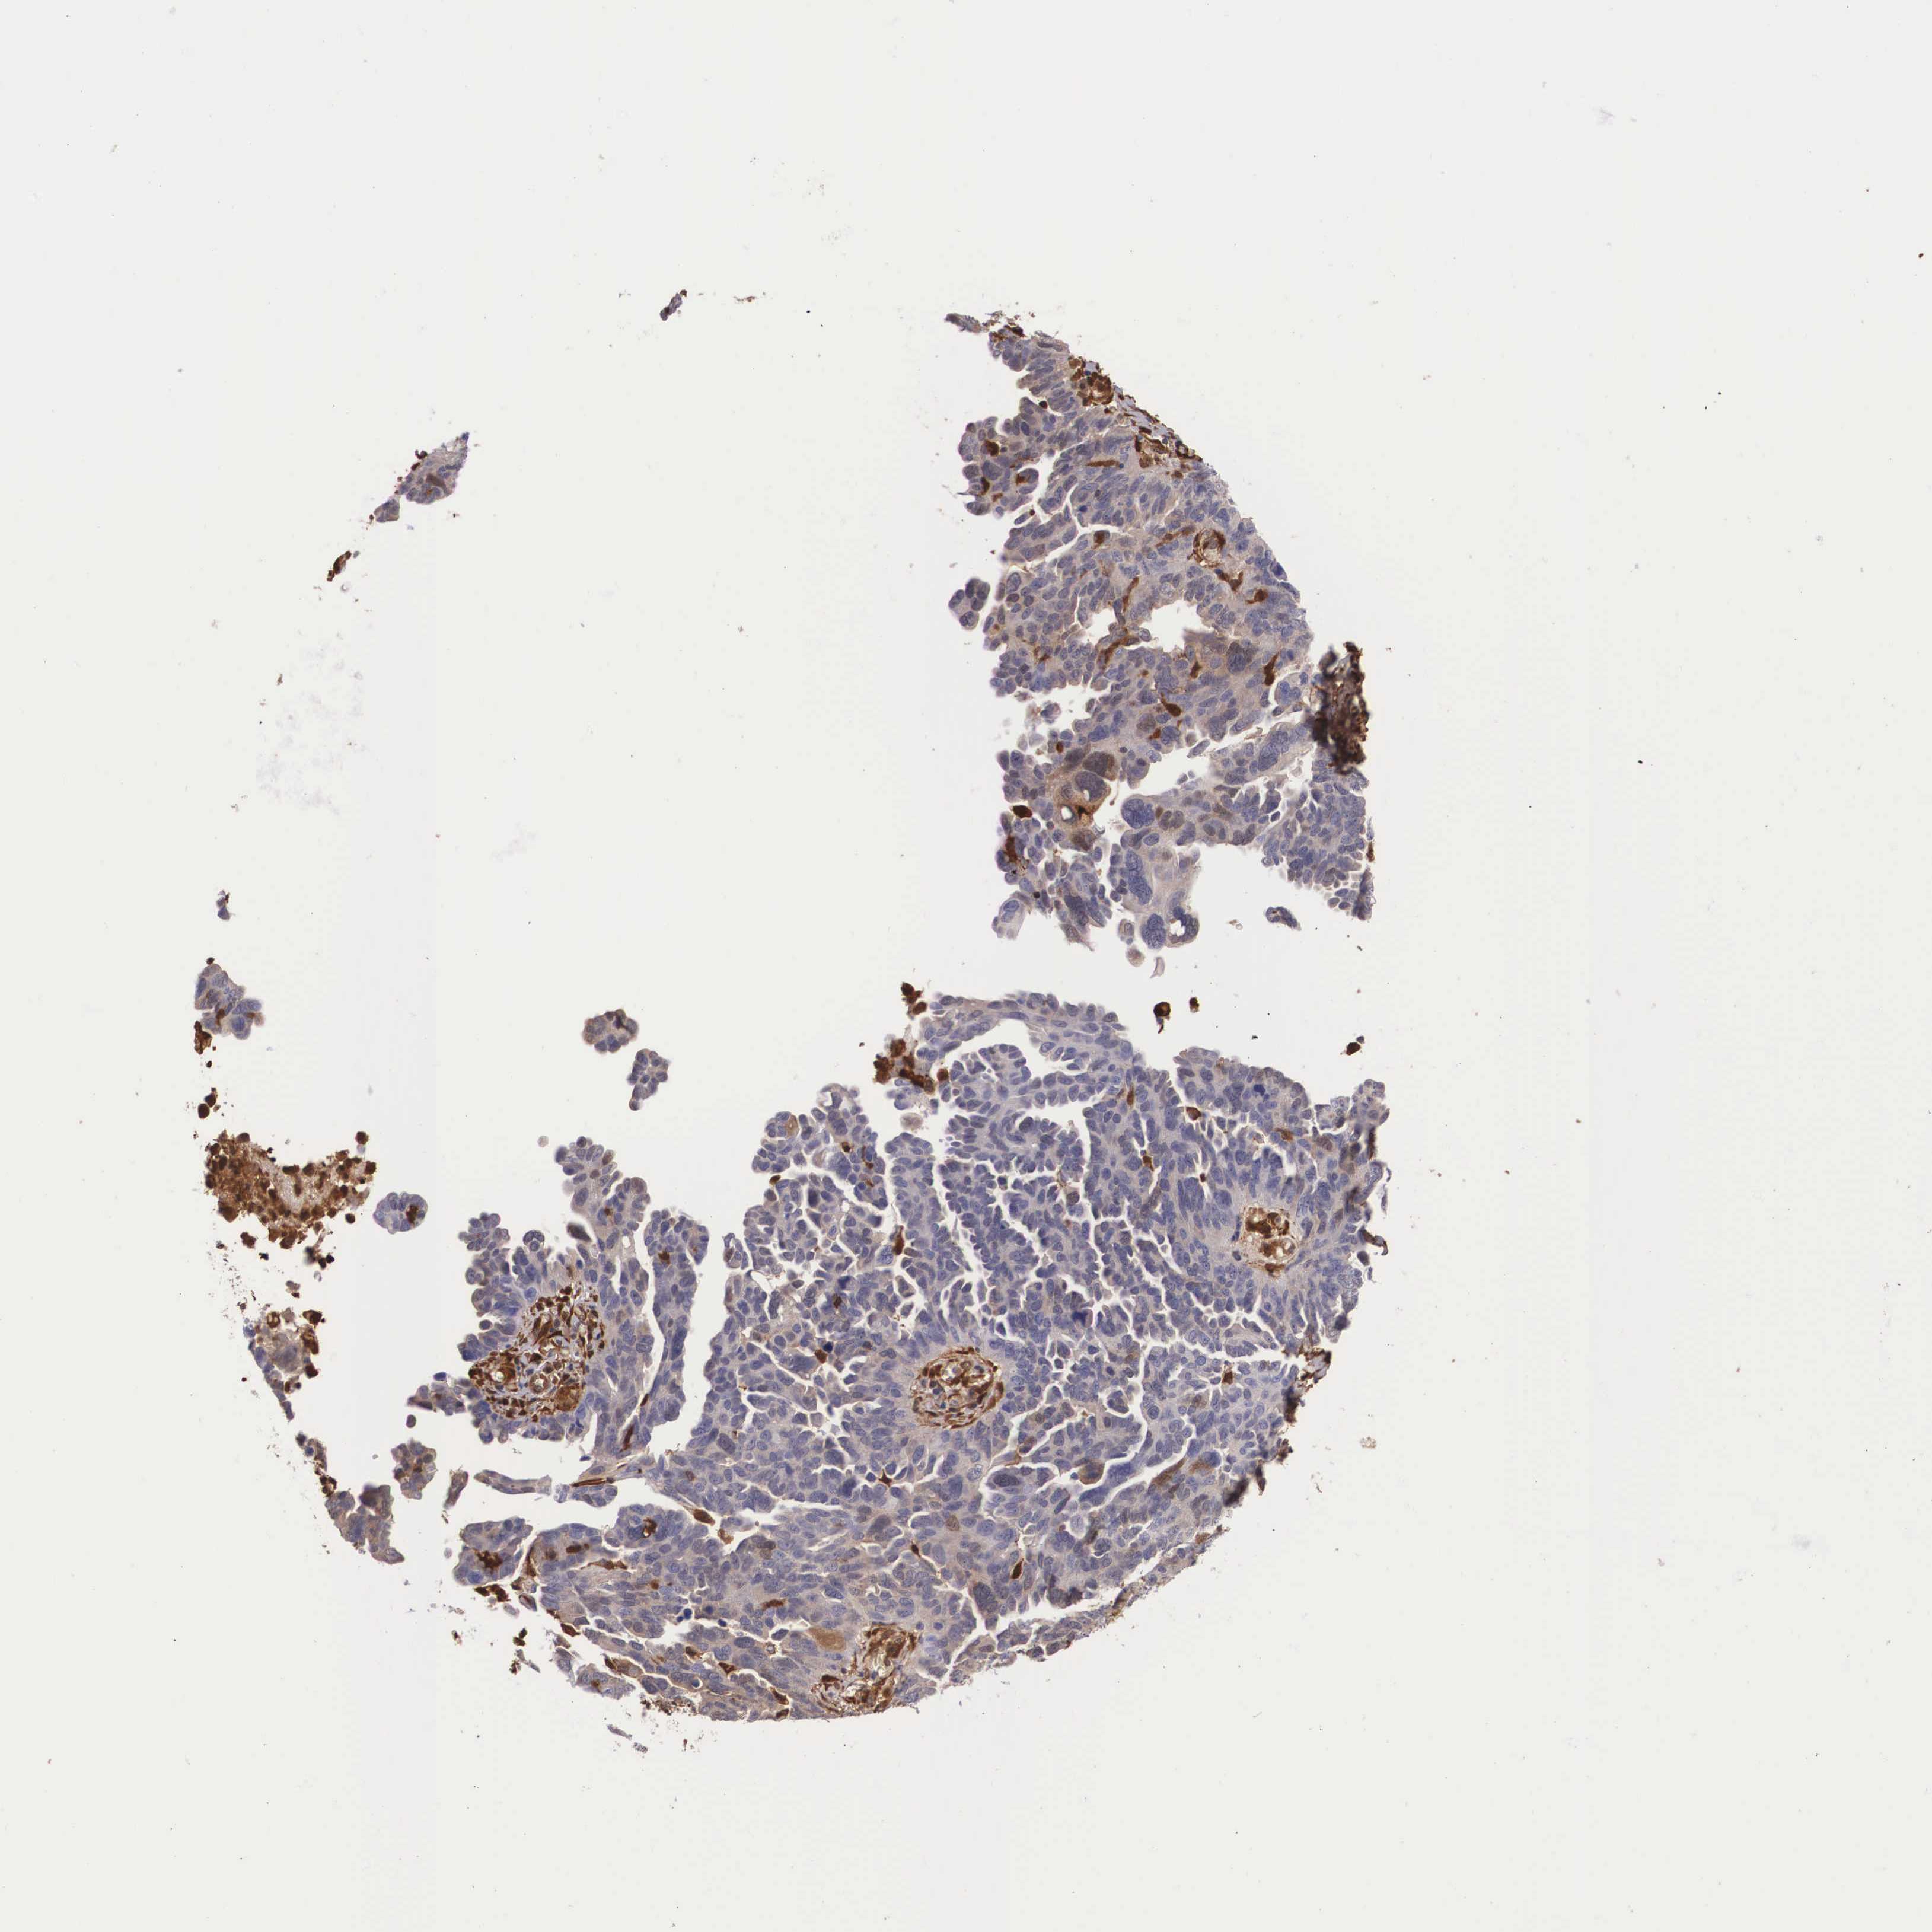

OVARIAN CANCER - Protein expressioni

A mouse-over function shows sample information and annotation data. Click on an image to view it in a full screen mode. Samples can be filtered based on level of antibody staining by selecting one or several of the following categories: high, medium, low and not detected. The assay and annotation is described here.

Note that samples used for immunohistochemistry by the Human Protein Atlas do not correspond to samples in the TCGA dataset.

Antibody stainingi

Antibody staining in the annotated cell types in the current human tissue is reported as not detected, low, medium, or high, based on conventional immunohistochemistry profiling in selected tissues. This score is based on the combination of the staining intensity and fraction of stained cells.

Each image is clickable and will lead to virtual microscopy that enables deeper exploration of all samples and also displays staining intensity scores, fraction scores and subcellular localization as well as patient and tissue information for each sample.

Antibody HPA000646

Antibody CAB002157

Carcinoma, endometroid

Cystadenocarcinoma, serous, NOS

Cystadenocarcinoma, mucinous, NOS